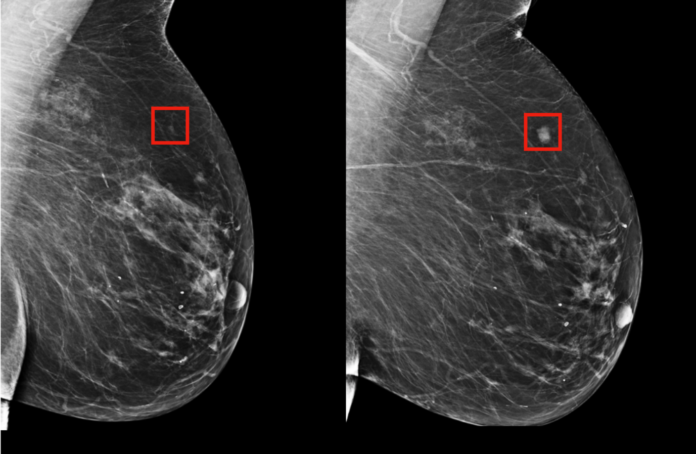

Lancet Oncology adlı hakemli dergide yayımlanan araştırmada İsveç’te ortalama 54 yaşındaki 80 binden fazla kadının mamografisi incelendi.

Görüntülerin yarısı normal prosedür olan iki radyolog tarafından incelenirken, diğer yarısı da yapay zeka tarafından incelendikten sonra bir veya iki radyoloğa sunuldu.

Standart yöntemde radyologlar 203 meme kanseri tespit ederken, yapay zeka 244 kadında meme kanseri olduğunu saptadı.